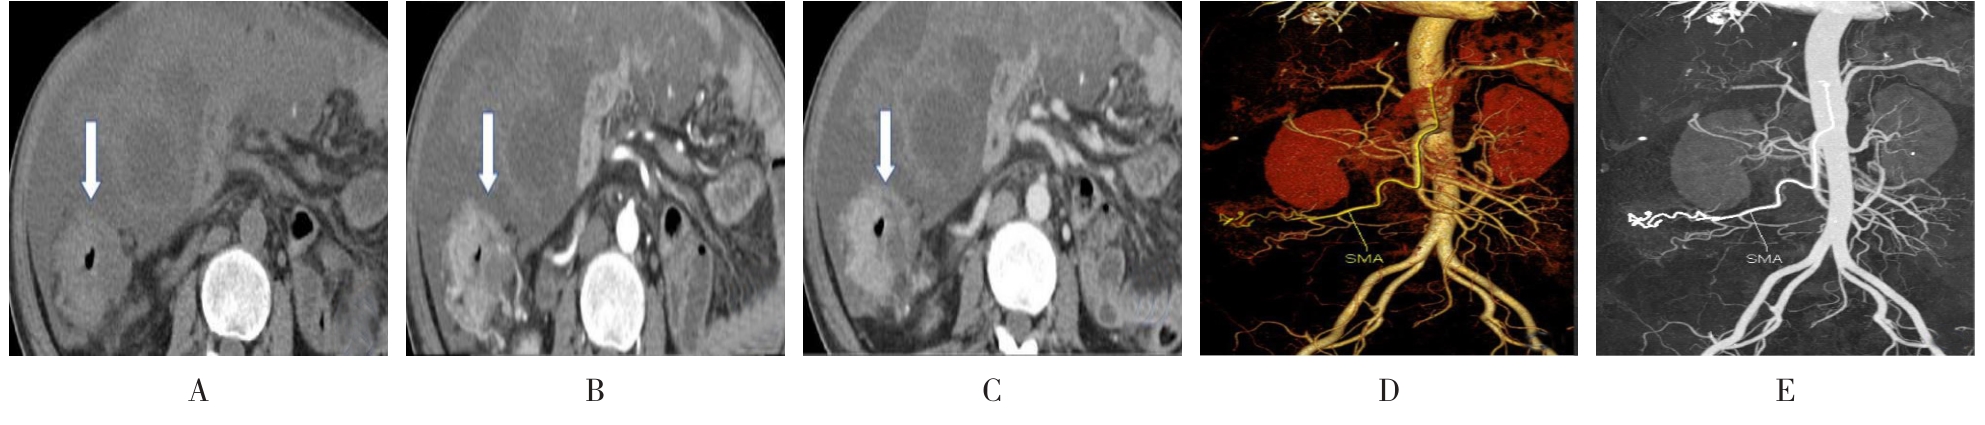

摘要:目的 分析计算机体层摄影血管造影(CTA)在腹腔镜结肠癌根治术前评估中的应用效果。方法 回顾性分析2021年1月-2024年2月于该院接受腹腔镜结肠癌根治术的120例患者的临床资料。其中,60例行常规腹部CT和CTA,60例行磁共振成像(MRI)。以术后病理为金标准,判断CTA对临床T分期与术后病理的一致性,以及评估肿瘤是否侵犯肠系膜血管和周围组织的准确度。结果 术前CTA诊断T分期的准确率为95.00%(57/60),一致性好(Kappa = 0.925,P < 0.05);术前MRI诊断结肠癌T分期的准确率为98.33%(59/60),两者比较,差异无统计学意义(χ2 = 0.26,P > 0.05)。CTA预判肿瘤是否累及肠系膜上动脉、肠系膜上静脉、肠系膜下动脉、肠系膜下静脉、腹主动脉、肾动脉、肾静脉和脾动脉等血管,与术后病理的一致性好。特别是在预测肠系膜血管受累方面,CTA的敏感度为94.44%,特异度为95.83%,准确度高达95.00%。结论 对于行腹腔镜结肠癌根治术的患者,术前CTA不仅能清晰地显示结肠癌T分期,还能揭示肠系膜血管的走行和变异,以及肿瘤与周围组织的关系和侵犯程度,从而为手术规划提供强有力的支持,确保了腹腔镜手术的安全性,减少了不必要的手术风险。